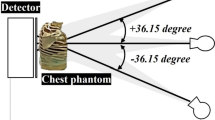

An automated TBE method for estimating the local noise in CT image in 3 steps was developed: (1) Partition the image into homogeneous and transition regions, (2) For each pixel in the homogeneous regions, compute the standard deviation in a \(15\times 15\times 1\) voxel local region using only pixels from the same homogeneous region, and (3) Interpolate the noise estimate from the homogeneous regions in the transition regions. Noise-aware fat segmentation was implemented. Experiments were conducted on the anthropomorphic phantom and in vivo low-dose chest CT scans to validate the TBE, characterize the magnitude of local noise variation, and determine the sensitivity of noise estimates to the size of the region in which noise is computed. The TBE was tested on all scans from the Early Lung Cancer Action Program public database. The TBE was evaluated quantitatively on the phantom data and qualitatively on the in vivo data.